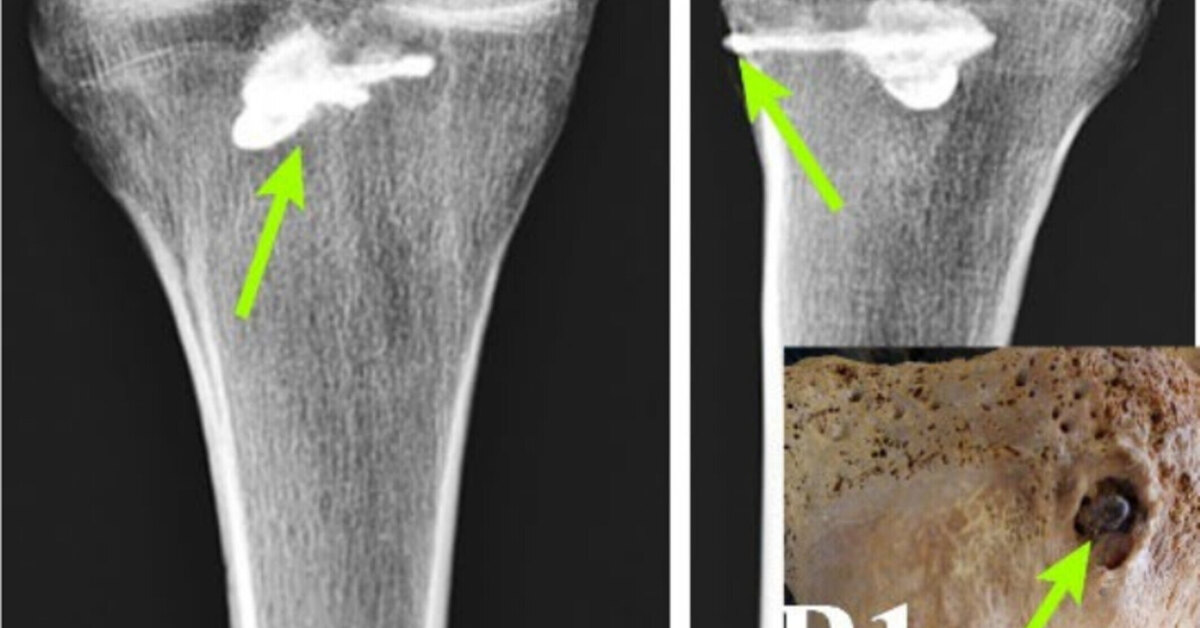

С помощью рентгенофлуоресцентного анализа — метода, определяющего химический состав вещества, — и компьютерной томографии ученые изучили сохранившиеся кости мужчины, а именно большеберцовую кость.

В ней они обнаружили металлический кусок стрелы. Это был не просто обломок, а целый наконечник с тремя лезвиями. Он был 44 мм в длину и 15 мм в ширину. Более того, его реконструкция полностью совпала по стилю с найденными ранее парфянскими стрелами.

Дальнейший анализ позволил ученым увидеть, что при жизни плотная костная ткань начала формироваться вокруг наконечника. Это означает, что после ранения человек остался жив, и его тело начало процесс заживления.